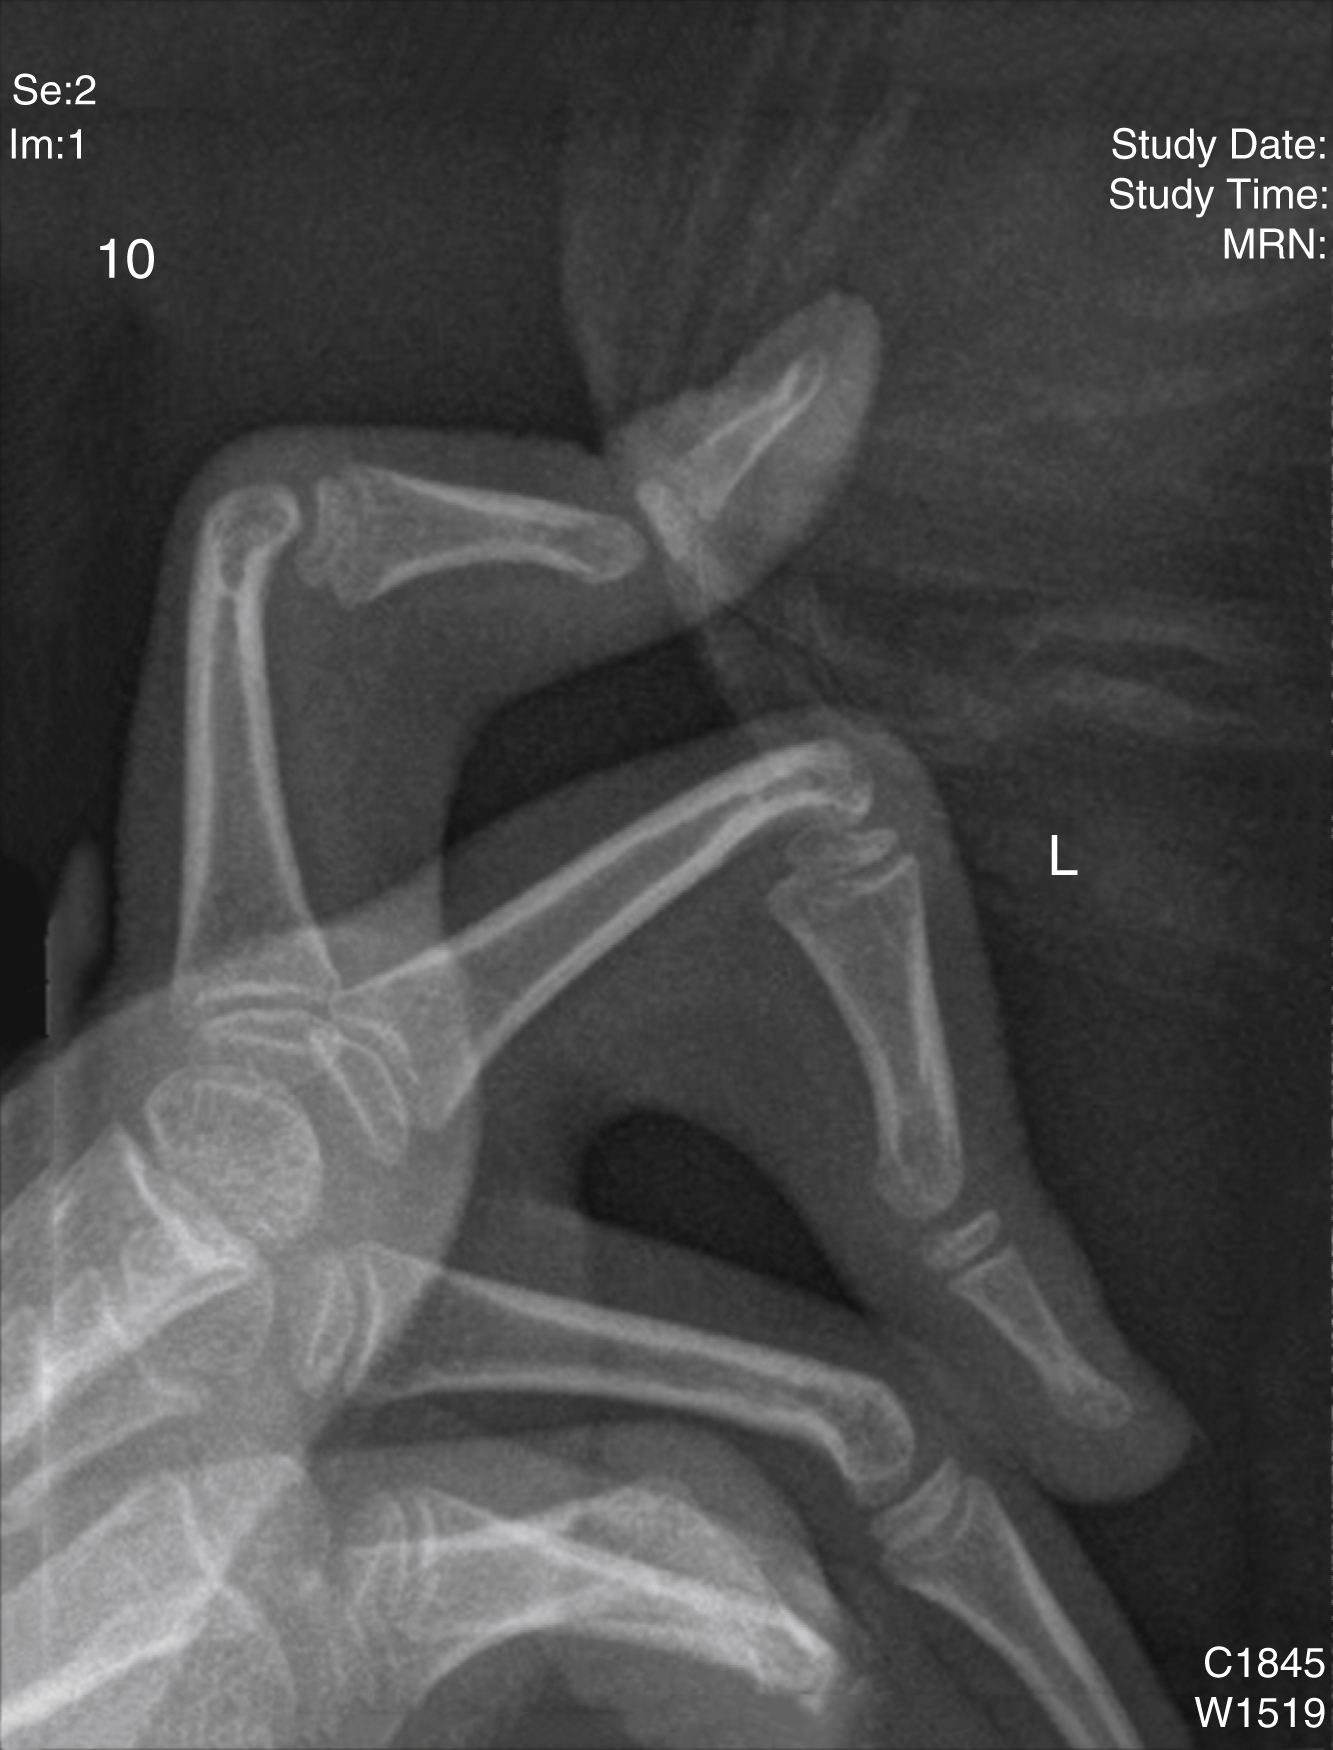

Syndactyly

A normal web ends at the midproximal phalanx on the volar side and an abnormal continuation beyond this level is termed syndactyly (Greek syn = together, dactylos = digit/finger). Syndactyly is the commonest congenital hand abnormality, with an incidence of 1 in 1000 live births. It is more common in Caucasians than Africans and affects males more than females (46%–84%). It is familial in 15%–40% and can be unilateral or bilateral (25%–50%). Syndactyly may affect the fingers and/or toes and most commonly presents as an incomplete second web syndactyly in the foot. In the hand, the third web is most frequently involved (50%) (see Fig. 45.2A, B ), followed by the fourth (30%), second (15%), and first (5%) %). A failure of apoptosis or programmed cell death, a process mediated by BMP-4 (bone morphogenic protein), is thought responsible during digit separation from day 41–53.

Syndactyly is classified as follows ( Fig. 45.2 ):

Incomplete or complete (extending to the distal phalanx)

Simple (soft tissue only) or complex (with bony synostosis)

Complicated (a haphazard arrangement of bones with loss of normal ray patterning)

Acrosyndactyly (fusion of digits distally, from the Greek acro meaning “tip,” with proximal fenestrations commonly associated with constriction ring syndrome).

Inspect the syndactylized digits. With complete syndactyly, the nails can be fused with an inward rotation of the digits, which eludes to the presence of a complex distal bony union ( Fig. 45.2C ). The degree of skeletal disruption within a syndactyly tends to parallel the degree of soft tissue abnormality, including that of tendons and digital neurovasculature structures. It is important to examine for the presence of digital creases, which provides valuable information about the passive and active joint range of motions, which may also be abnormal. The status of the joints pre-separation must be established to ensure adequate counseling of patients and their families with regard to the postoperative motion and function. Often a child and family will opt for the correct complement of digital number over function in equivocal cases.

In complicated syndactyly there is more than just a bony synostosis. Often there is a haphazard arrangement including extra skeletal elements concealed within a digit with associated fusions, rudimentary bones, missing bones, abnormal joints, and sometimes cross bones, which can span several rays ( Fig. 45.2D ). It can be uncertain which bones best match with which digits. In acrosyndactyly, there is a complex syndactyly characterized by fusion of the bone distally but not proximally with often fenestrations or sinuses proximally ( Fig. 45.2E ). This is discussed later under Constriction Ring Syndrome (CRS).